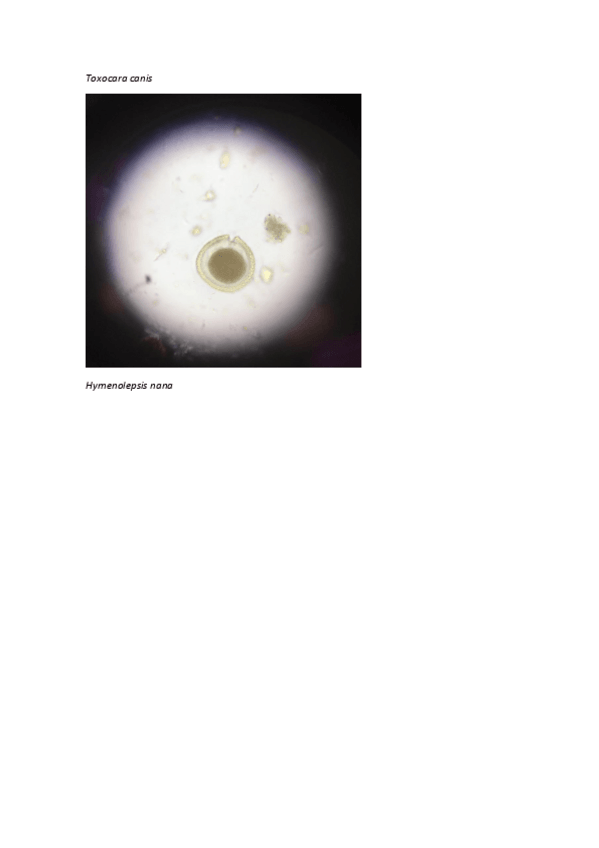

He publicado nuevos apuntes de 1º Parasitología: ParasitologiaCuadernoPracticas.pdf

He publicado nuevos practicas de 1º Parasitología: 1o-sesion-parasitologia.pdf

4 páginas

He publicado nuevos practicas de 1º Parasitología: 5o-sesion-parasitologia.pdf

11 páginas

He publicado nuevos practicas de 1º Parasitología: 4o-sesion-parasitologia.pdf

6 páginas

He publicado nuevos practicas de 1º Parasitología: 3o-sesion-parasitologia.pdf

5 páginas

He publicado nuevos practicas de 1º Parasitología: 2o-sesion-parasitologia.pdf

7 páginas